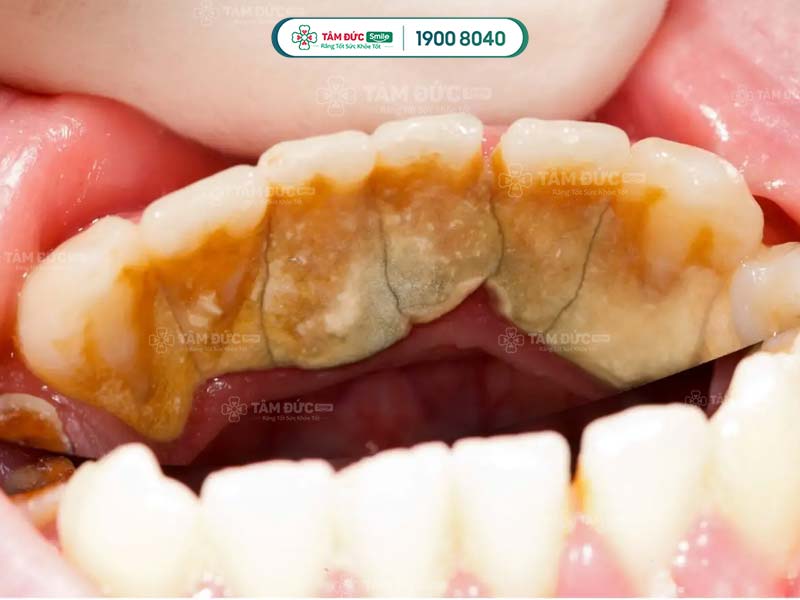

- Phát hiện có nhiều cao răng và mảng bám ở thân răng hoặc dưới nướu.

Cao răng không phải là nguyên nhân trực tiếp gây ra các bệnh lý về răng miệng, nhưng lại là nơi trú ngụ của nhiều loại hại khuẩn. Vì vậy, cao răng tạo điều kiện để vi khuẩn gây bệnh.

Cao răng tích tụ lâu ngày sẽ gây ra các bệnh lý như: Sâu răng, viêm nướu, tụt nướu, mòn men răng, viêm nha chu,... Do đó, cạo cao răng thường xuyên giúp Quý khách ngăn chặn vi khuẩn phát triển, giảm nguy cơ mắc phải các bệnh lý răng miệng.

Vi khuẩn tích tụ trong cao răng thời gian dài sẽ tấn công vào sâu bên trong, làm hư hại răng và nướu nặng nề. Lâu dần, xương hàm của Quý khách có thể bị tiêu biến, tăng nguy cơ lung lay răng vĩnh viễn. Như vậy, cao răng nghiêm trọng có thể làm cho Quý khách đối mặt với vấn đề mất nhiều răng cùng lúc.